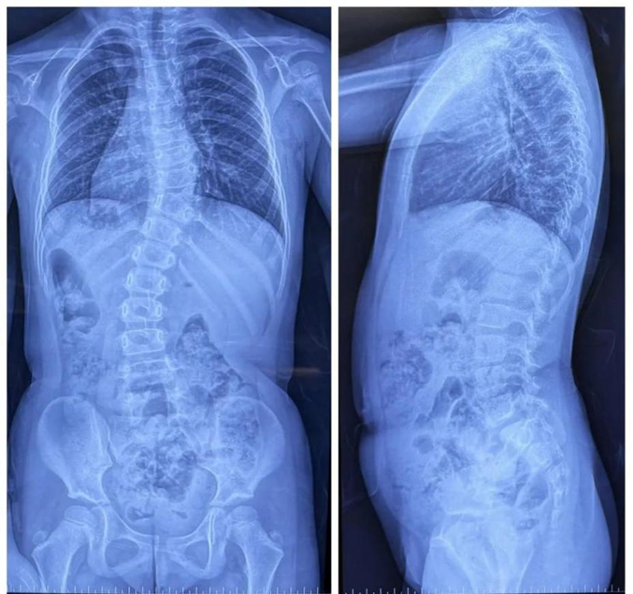

Children's Hospital of Nanjing Medical University successfully completed this highly complex surgical procedure through the integrated application of Perlove Medical's 3D C-arm and surgical robot, demonstrating optimal synergy between intelligent technology and surgical expertise.

01 Precision Navigation

During the surgery, the medical team used the Perlove Medical’s flat-panel 3D C-arm to acquire 3D and CT-like images of the patient, enabling comprehensive visualization of the pedicles. Guided by the robot's 3D planning system, the surgeon mapped each screw's ideal path and angle to achieve maximum screw purchase strength and improve spinal stability by accommodating the unique biomechanical properties of pediatric bone tissue.

One-time planning for quadruple K-wire insertion

The robotic arm enhanced stabilization of surgical instruments, enabling precise execution. Guided by pre-planned trajectories, the system achieved accurate single-attempt pedicle screw placement within narrow vertebral pedicles - effectively navigating the 'anatomical labyrinth'. This approach eliminated risks associated with repeated positioning attempts. The fully integrated system demonstrated perfect coordination, successfully completing the implantation of four pedicle screws with sub-millimeter accuracy.

02 Radiation Safety

Addressing common parental concerns about radiation exposure, traditional K-wire insertion requires separate AP/lateral imaging for each of the four insertion points - with repeated X-ray verification. In contrast, the orthopedic robot utilizes a 'single 3D scan for complete trajectory planning' protocol. When integrated with Perlove Medical's 3D C-arm pulsed fluoroscopy mode, this approach significantly reduces total radiation dosage, effectively mitigating radiation risks.